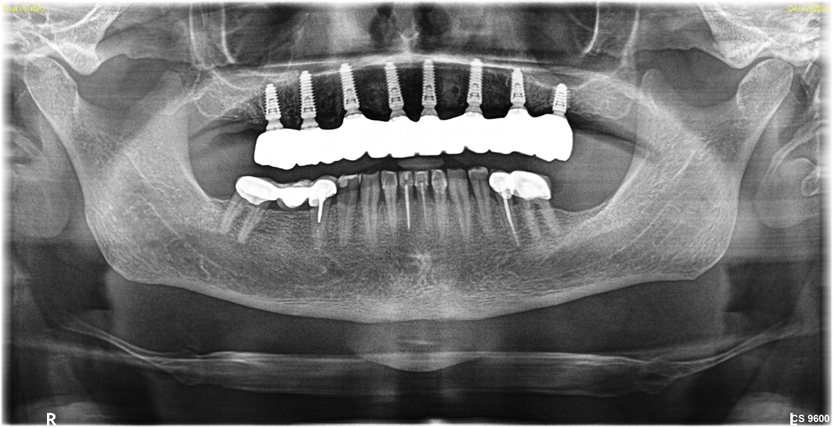

Importantly, patients for whom implant placement is being planned may have previously undergone root canal treatment utilizing radio-opaque materials or have amalgam, metal, or metallo-ceramic restorations, or they may even have previous implants. When x-ray beams pass through these radio-opaque objects, the resulting CBCT images often have metallic scatter (Figure 1, left panel). The artifacts or noise created by the metallic or metallic-like substances degrade the image quality and induce cupping or streaks. This can be particularly troublesome when the clinician is attempting to diagnose dental conditions or to fabricate surgical guides.

Previous CBCT softwares utilized the FDK (Feldkamp, Davis, and Kress) algorithm or SART (simultaneous algebraic reconstruction technique ).12 For many years, the quality of CBCT scans required additional steps to reduce the amount of scatter; often a tray or fiducial device would be required in the CBCT patient capture and again in a standalone capture. However, advancements in CBCT such as metal artifact reduction (MAR)13 (Figure 1, right panel) and beam hardening removal have helped address these challenges in obtaining high-quality scans. Projection-based MAR algorithms act in projection space and replace corrupted projections caused by metal with interpolation from neighboring uncorrupted projections. By reducing scatter and artifacts, these enhanced tools of MAR allow for a simplified matching between 3D radiography and the digital impressions, allowing users to expedite planning and treatment as a whole. Once the files have been merged, proper treatment planning can begin.

Fig 1. CBCT using the Feldkamp, Davis, and Kress (FDK) algorithm (left panel) and metal artifact reduction (MAR) algorithm (right panel). Note

the visible scatter and hardening associated with FDK is absent when MAR is used, and the bone quality is sharper and more defined with the

MAR image.